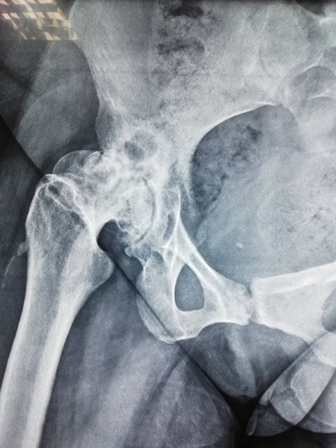

Ασθενής 34 ετών μετά από τραυματική επιφυσιολίσθηση σε ηλικία 11 ετών με αποτυχημένη αντιμετώπιση